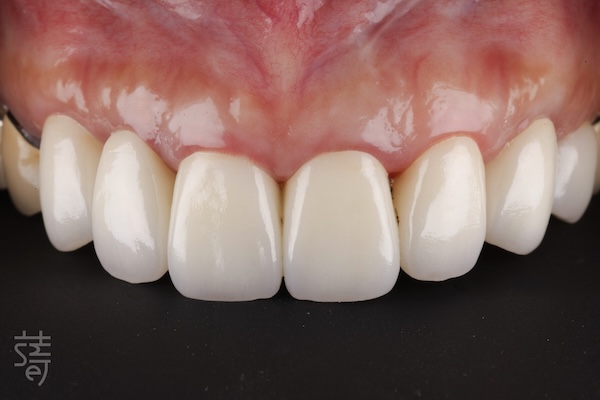

第四階段 全瓷美學,重現自然笑容

Stage Four: All-ceramic artistry — restoring a natural smile

植牙完成後,臨時假牙逐步更換為全瓷牙套。

紀醫師與蒔美數位牙技中心協作,精準微調牙色、形態與笑容曲線。全瓷材質呈現真牙般透明感與光澤,燈光下依舊自然。

每個階段間保留足夠癒合與觀察時間,骨與牙齦穩定生長。最終完成的全瓷牙冠在外觀與功能上達到完美平衡,笑容柔和流暢,自然、自信重現。

After the implants healed, temporary restorations were gradually replaced with custom all-ceramic crowns.

Working closely with the Smile Digital Dental Center, Dr. Chi fine-tuned each detail—from tooth shade to contour and smile line. The all-ceramic material reflected light like natural enamel, giving the teeth a lifelike translucency under any lighting.

Each stage allowed ample time for healing and adjustment, ensuring the bone and gums integrated stably. The final result achieved a seamless harmony between aesthetics and function—a soft, confident smile that felt entirely her own.

久違了!全口植牙重建讓笑容與生活回歸

A Long-Awaited Return: Full-Mouth Reconstruction Restores Smile and Life

重建前,陳太太吃東西總覺得不舒服,笑起來也好尷尬。聚餐時,她不自覺縮小笑容,生怕牙齒鬆動或咬不斷食物。

In the past, Mrs. Chen struggled to eat comfortably, and her smile felt awkward. At gatherings, she would hold back, worried her teeth might feel loose or fail to bite through food.

如今,完整的全口植牙重建讓她能大口咀嚼喜愛食物,也能毫不顧忌地開懷大笑。「現在感覺就像自己的牙齒,非常自在。」她笑著分享。

Now, with full-mouth implants, she can enjoy her favorite foods and laugh freely. “It feels just like my own teeth—so natural,” she shares.

從舒眠治療、導航植牙、即拔即植,到全瓷美學修復,每一步都由醫師團隊細心規劃。這不只是牙齒的重建,更是生活品質的回歸:重新擁有自信笑容、自在進食,找回健康與從容日常。

From sedation and guided implant placement to immediate implants and full-ceramic restoration, every step was carefully planned. This reconstruction isn’t just about teeth—it’s a return to quality of life: confident smiles, comfortable eating, and reclaiming her sense of ease and well-being.